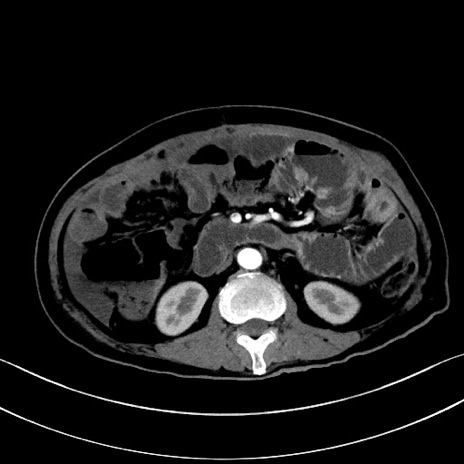

冠状断像

【症例】60歳代男性

【主訴】嘔吐

【現病歴】胃癌にて胃全摘後。食思不振が悪化し、夜中に嘔吐することがある。

【既往歴】胃癌、胃全摘、脾摘、胆摘後

【データ】WBC 5900、CRP 10.56